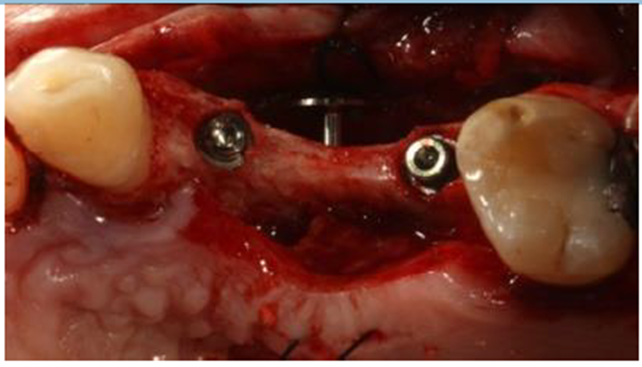

Para corrigir a deficiência residual foi utilizado um parafuso de cabeça expandida de 5,7 mm de diâmetro (Implacil De Bortoli – São Paulo – Brasil), que foi instalado com contra ângulo redutor, montado em motor elétrico com torque de 60 Ncm e com velocidade de 60 RPM (Figura 7).